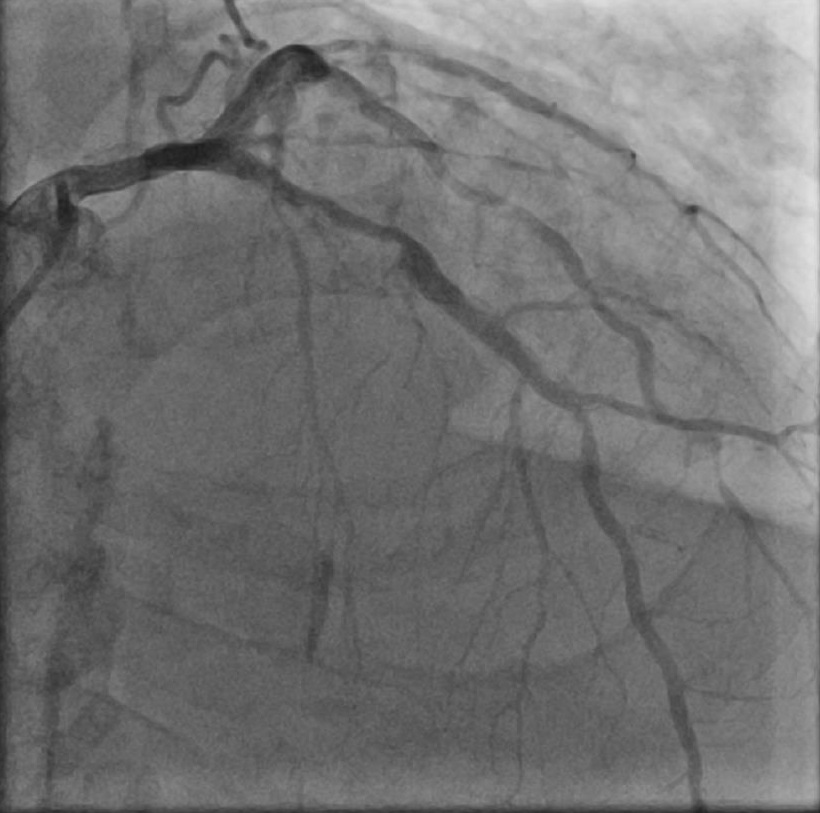

心电图提示广泛ST-T改变。经加强透析、抗感染等治疗改善心衰后,行冠脉造影提示三支病变,冠脉严重钙化,左前降支-左主干最严重,显示多处弥漫狭窄、钙化,前降支中段狭窄80%,左主干根部分叉狭窄70%狭窄。

术后造影图像